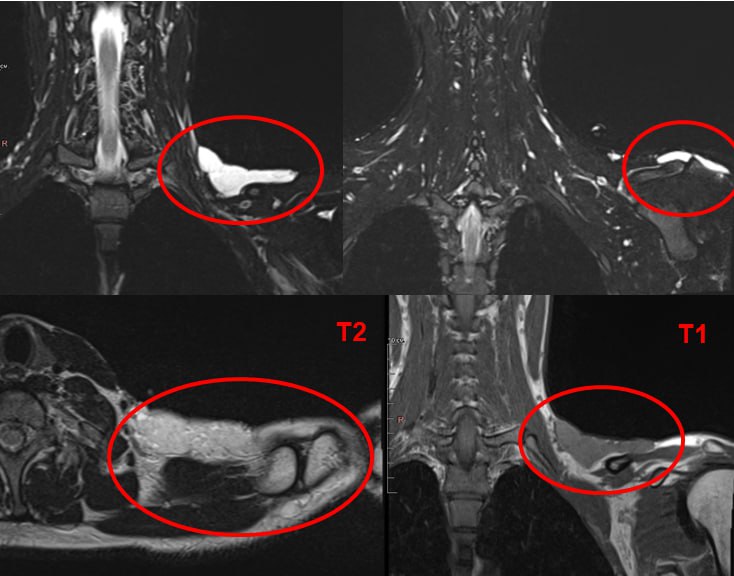

В результате обследования специалисты выявили в надключичной области жидкостное образование неоднородной структуры. На основании полученных изображений был поставлен предварительный диагноз — гемангиома или лимфатическая мальформация.